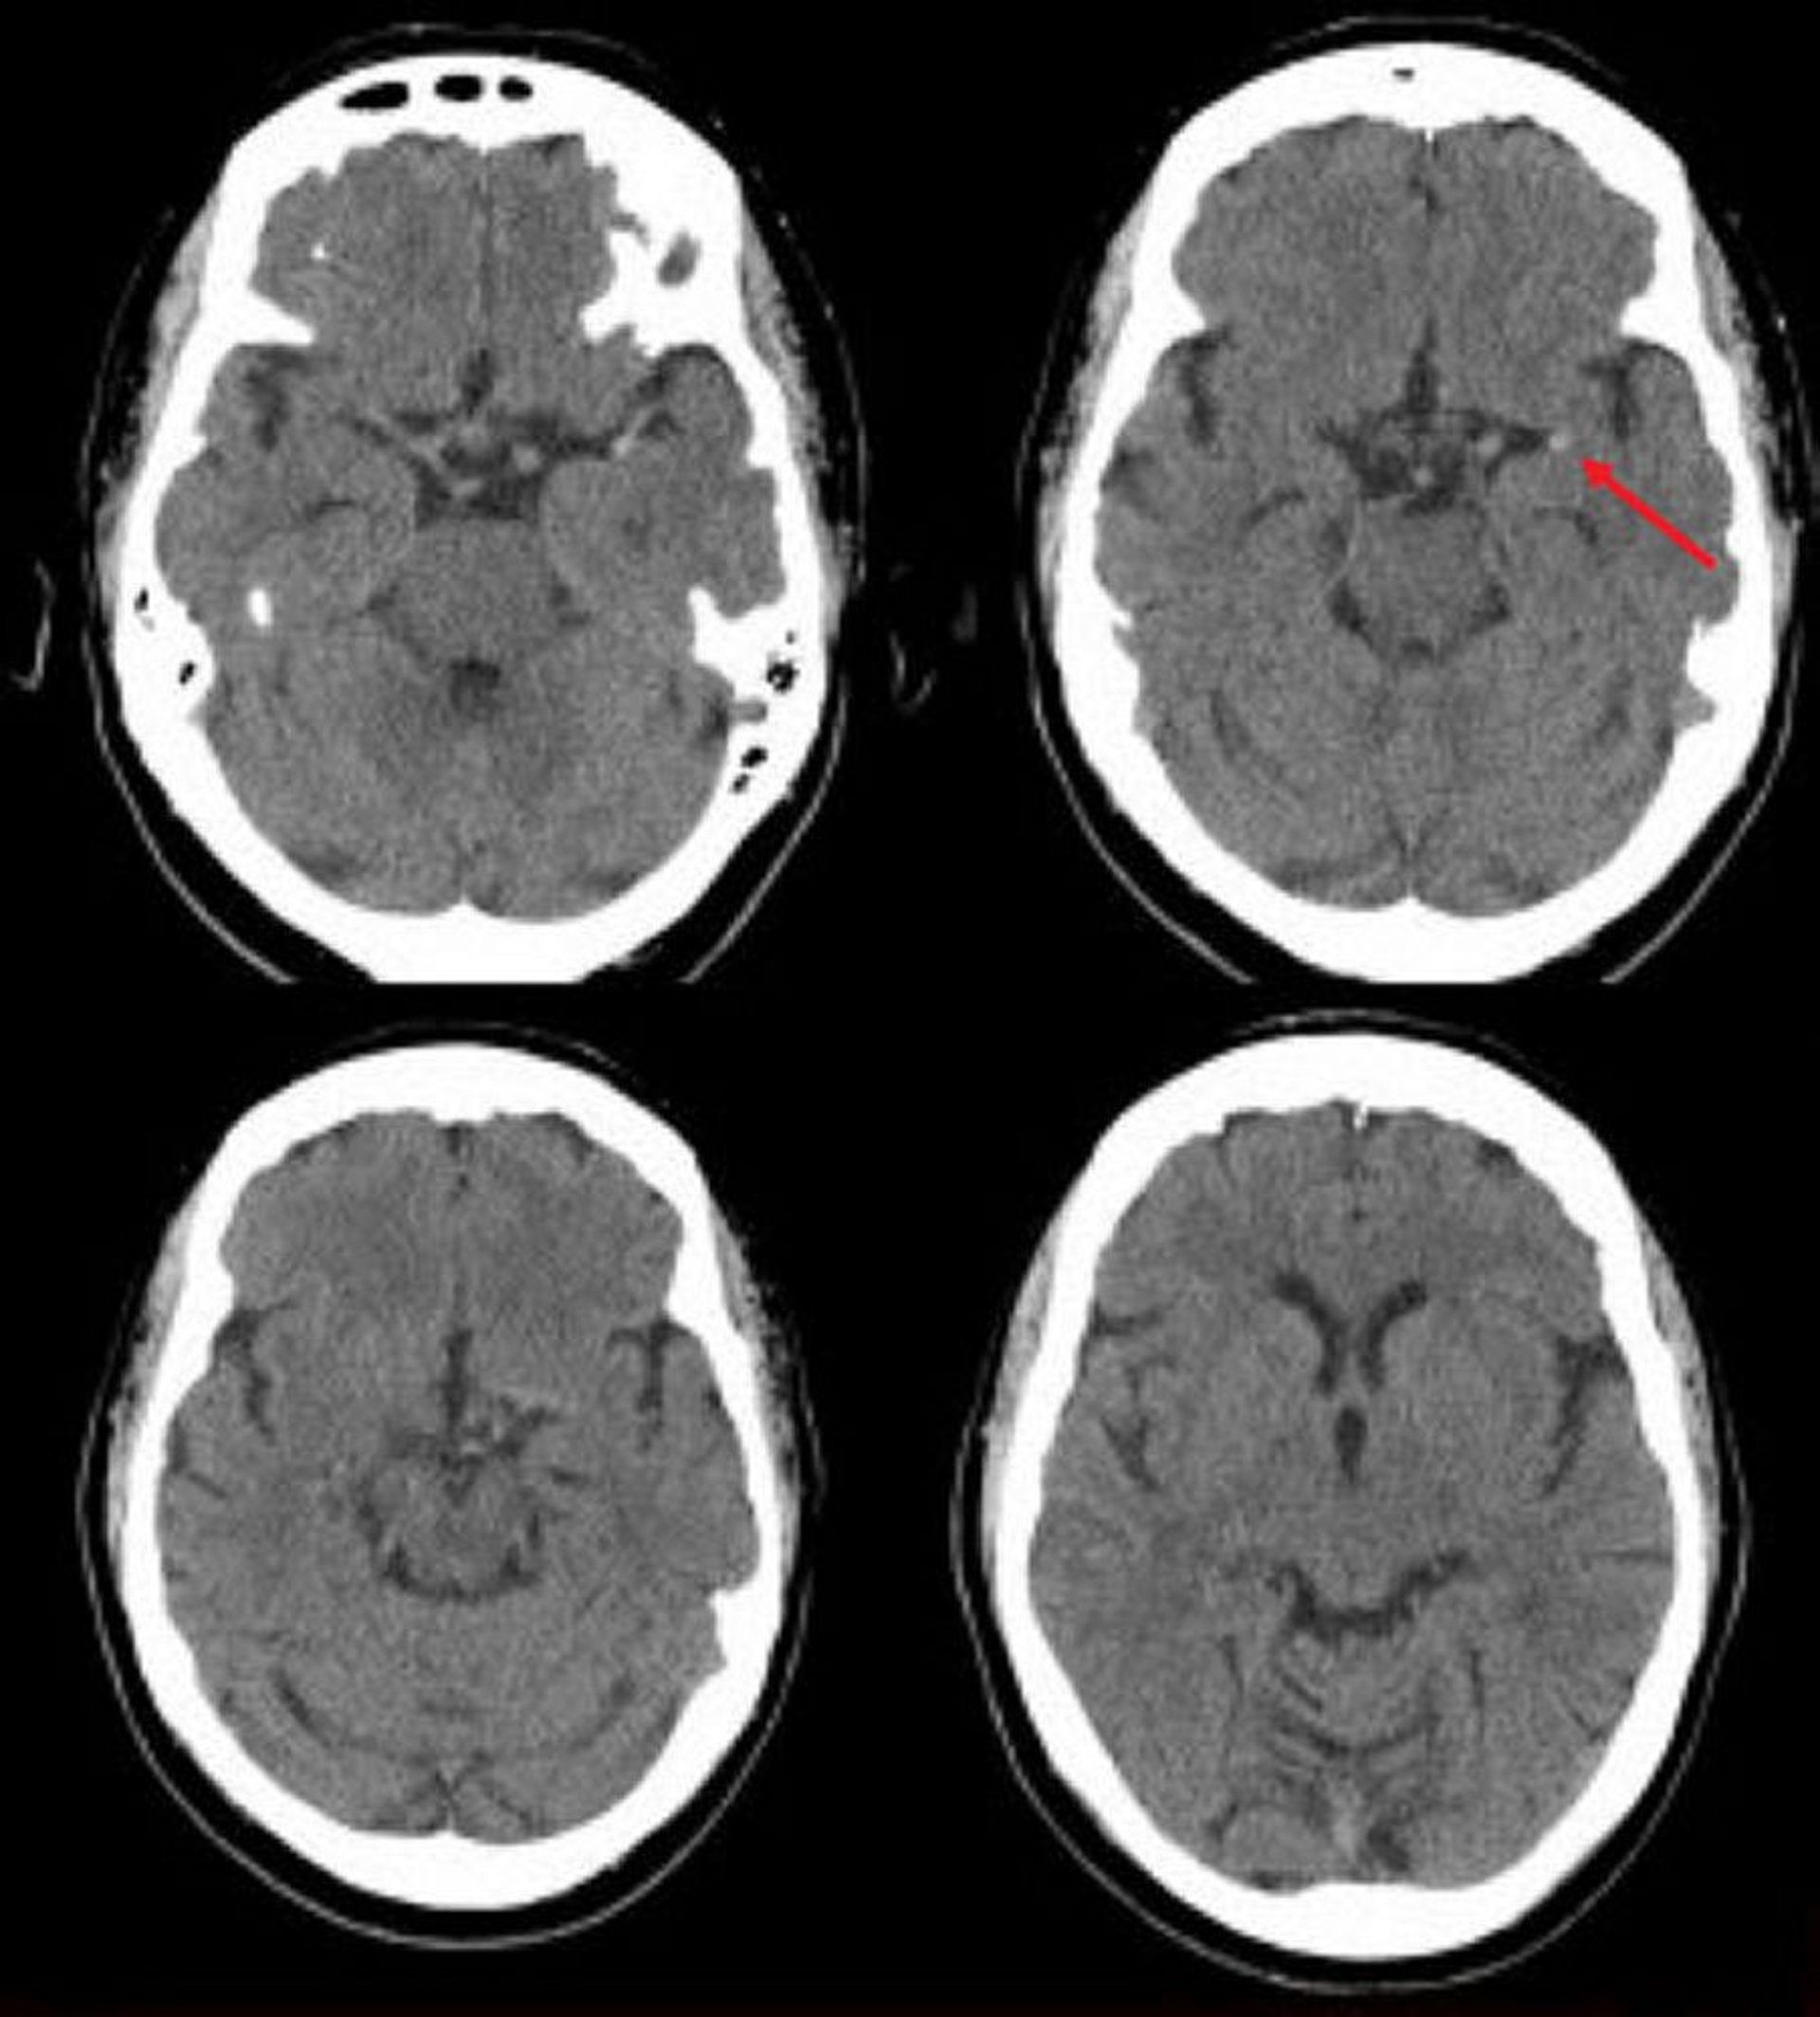

Ішемічний інсульт у лівій середній мозковій артерії (КТ)

This noncontrast head CT scan shows a hyperdense left middle cerebral artery. This finding indicates a focal clot in the left middle cerebral artery (arrow).

Image courtesy of Ji Y. Chong, MD.